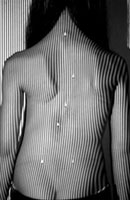

Возможность использования топографического мониторинга состояния больных сколиозом взамен рентгена была изучена на основе клинического материала школы-интерната №133 для детей больных сколиозом г.Новосибирска, где, начиная с 1995 года, проводились ежегодные обследования на ТОДП постоянного контингента больных параллельно с рентгеном. Среди больных по характеру течения заболевания выделены 3 группы: СФ - стабильная форма сколиоза, УПФ - умеренно прогрессирующая, БПФ - быстро прогрессирующая форма. Пример наблюдения больной с быстро прогрессирующей формой сколиоза приведен на рисунках ниже.

9,0 лет 10,4 лет 10,8 лет 11,4 лет 12 лет

PTI=1,0; Cobb=10° PTI=1,3; Cobb=17° PTI=1,9; Cobb=23° PTI=2,9; Cobb=38° PTI=3,6; Cobb=55°

За трехлетний период наблюдения в возрасте с 9 до 12 лет основная правосторонняя грудная дуга по углу Кобба спрогрессировала с 10 до 55°, т.е. средняя скорость прогрессирования составила 15° в год. Общий индекс нарушения формы дорсальной поверхности туловища PTI изменился с 1,0 (граница нормы и умеренно выраженных отклонений) до 3,6 (значительное отклонение). Следует обратить внимание, что в начале наблюдения туловище больной имело хороший баланс во фронтальной плоскости (вертикальная ось, проходящая через вершину межъягодичной складки, проходит также и через C7), а с возраста 10,8 лет стало явно нарастать нарушение баланса с отклонением туловища вправо, т.е. в сторону выпуклости основной дуги. Приведенный пример убедительно демонстрирует наглядность топографических данных и их большую информативность для решения задачи неинвазивного мониторинга состояния больных сколиозом.